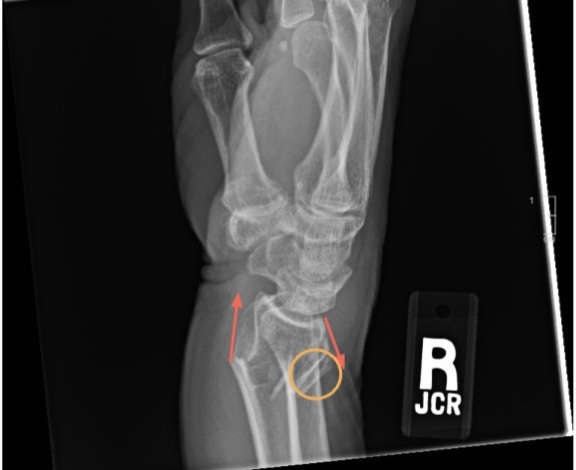

A 64-year-old female patient presents to the ED, complaining of wrist pain, with visible guarding of the area. Earlier in the day, while ice skating, the patient, in an effort to break her fall, outstretched her hand and fell onto her wrist, resulting in the fracture. The patient’s vitals were measured as normal in regards to saturation (on room air), blood pressure, mean arterial pressure, temperature, pulse, and respiratory rate. Following an initial physical examination, soft tissue swelling was observed in the right/left wrist, the area of impact regarding the injury. No further injuries were observed and the patient was observed as alert and responded to stimuli. Although, as determined from the initial physical examination and the signs and symptoms observed, a wrist fracture was likely, the patient was sent to radiology to confirm the suspected finding, classify the injury further, and observe any other injuries overlooked by the physical examination. The x-ray featured an obvious DRF indicated by a clear fracture, displacement of radial bone, and angular distortion (Figures 1 & 2).

A type of FOOSH injury, DRFs are diagnosed based on physical examination and plain radiography, which is used to further clarify the location and extent of the fracture, thus dictating the treatment provided. In x-rays, DRFs commonly present with dorsal angulation of the fractured distal fragment. Radiographic assessment aids, in conjugation with physician physical examination, aid in preoperative planning and long-term healing efforts.12 Depending on the severity of the injury, treatment plans may differ. Initial treatment of DRFs include splinting the wrist, icing the injured area to prevent swelling, and the administration of painkillers, if needed. Additionally, follow up consultations are usually scheduled with orthopedic specialists. Based on radiographic findings and orthopedic consultations, casts may be applied, and in extreme cases surgical intervention may be necessary to correct the fracture.13 Definitive treatment depends on a number of factors, with the most common being: severity of fracture, displacement of fractured bone, and lifestyle and age of patient. In most cases, non-operative treatment with casting is the preferred choice for non-displaced fractures. However, for more severe fractures may necessitate open reduction and internal fixation to help realign and stabilize.14 Additionally, if necessary, surgical intervention by means of percutaneous pinning, and internal fixation using plates or screws, and closed reductions may be utilized durinrg the process.